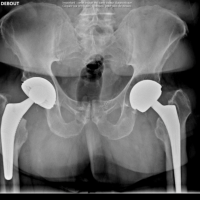

Information médicale complète à destination des patients Cette page a pour objectif de fournir une information claire, détaillée et approfondie sur la reprise de prothèse totale de hanche, également appelée chirurgie de révision de prothèse de hanche. Elle s’adresse aux patients porteurs d’une prothèse de hanche qui présentent des douleurs persistantes, une perte de fonction, une instabilité ou une complication...